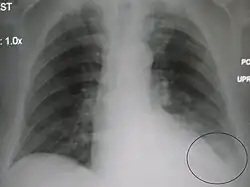

Pleural effusion

With pleural effusion, fluid often builds up in the costophrenic angle (due to gravity). This can push the lung upwards, resulting in "blunting" of the costophrenic angle. The posterior angle is the deepest. Obtuse angulation is sign of disease.

Chest x-ray is the first test done to confirm an excess of pleural fluid. The lateral upright chest x-ray should be examined when a pleural effusion is suspected. In an upright x-ray, 75 mL of fluid blunts the posterior costophrenic angle. Blunting of the lateral costophrenic angle usually requires about 175 mL but may take as much as 500 mL. Larger pleural effusions opacify portions of the hemithorax and may cause mediastinal shift; effusions > 4 L may cause complete opacification of the hemithorax and mediastinal shift to the contralateral side.